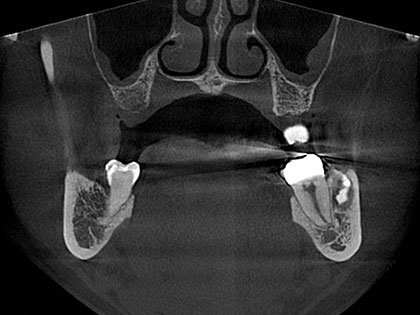

• インプラント術前2